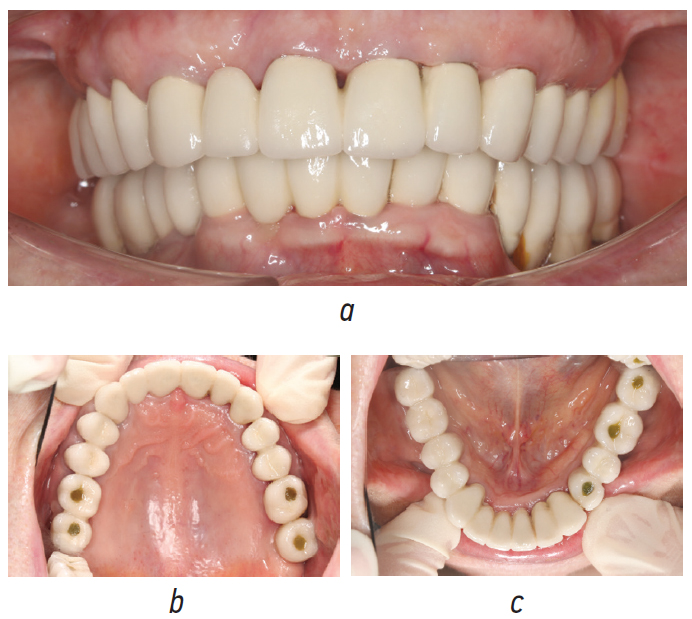

After 4 months of using the temporary structures, the fabrication and fitting of the permanent dentures with tooth and implant support were completed (Fig. 11).

Fig. 11. Permanent metal-ceramic structures based on the teeth and implants: a, anterior projection; b, occlusal projection of the upper dentition; c, occlusal projection of the lower dentition

Рис. 11. Постоянные металлокерамические конструкции с опорой на зубы и имплантаты: a — передняя проекция, b — окклюзионная проекция верхнего зубного ряда, c — окклюзионная проекция нижнего зубного ряда

The patient is currently satisfied with the prosthetics and does not have any complaints related to the masticatory apparatus.